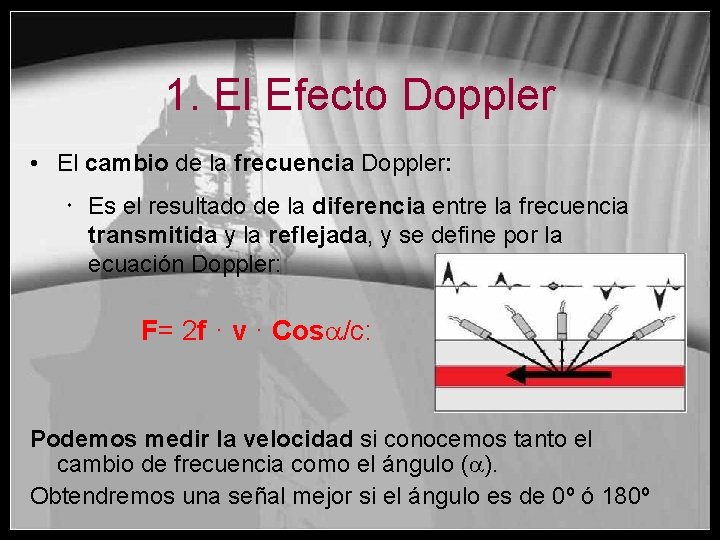

1. El Efecto Doppler • El cambio de la frecuencia Doppler: Es el resultado de la diferencia entre la frecuencia transmitida y la reflejada, y se define por la ecuación Doppler: F= 2 f · v · Cos /c: Podemos medir la velocidad si conocemos tanto el cambio de frecuencia como el ángulo ( ). Obtendremos una señal mejor si el ángulo es de 0º ó 180º

1. El Efecto Doppler • La variación de la frecuencia del Doppler es: Es directamente proporcional a la frecuencia emitida y a la velocidad de la estructura estudiada Está en relación con el coseno del ángulo Doppler ( ), el cual es necesario para medir correctamente las velocidades • Las mediciones obtenidas utilizando ángulos pequeños (<60º) provocan grandes cambios en la frecuencia Doppler. El mayor cambio en la frecuencia Doppler ocurre cuando la sangre se mueve directamente hacia el transductor o en contra de este, por tanto: Es mejor si =0 ó =180

1. El Efecto Doppler • Sin embargo cuando el ángulo es cercano a 90º el coseno y por tanto la diferencia entre frecuencias se reduce: Coseno de 90º = 0 • Si la sangre se mueve perpendicularmente al transductor, el flujo no se detecta porque no provoca ningún cambio en la frecuencia Doppler. (cos 90=0) F= 2 f · v · Cos /c F = 0 !!! = 90º Cos = 0 Flujo sanguíneo

1. El Efecto Doppler • Para obtener una buena señal Doppler es necesario conseguir un ánglulo menor a 60º F= 2 f · v · Cos /c BIEN = 60º Flujo sanguíneo Cos = 0, 5 F= 2 f · v · Cos /c MEJOR = 30º Flujo sanguíneo Cos = 0, 87